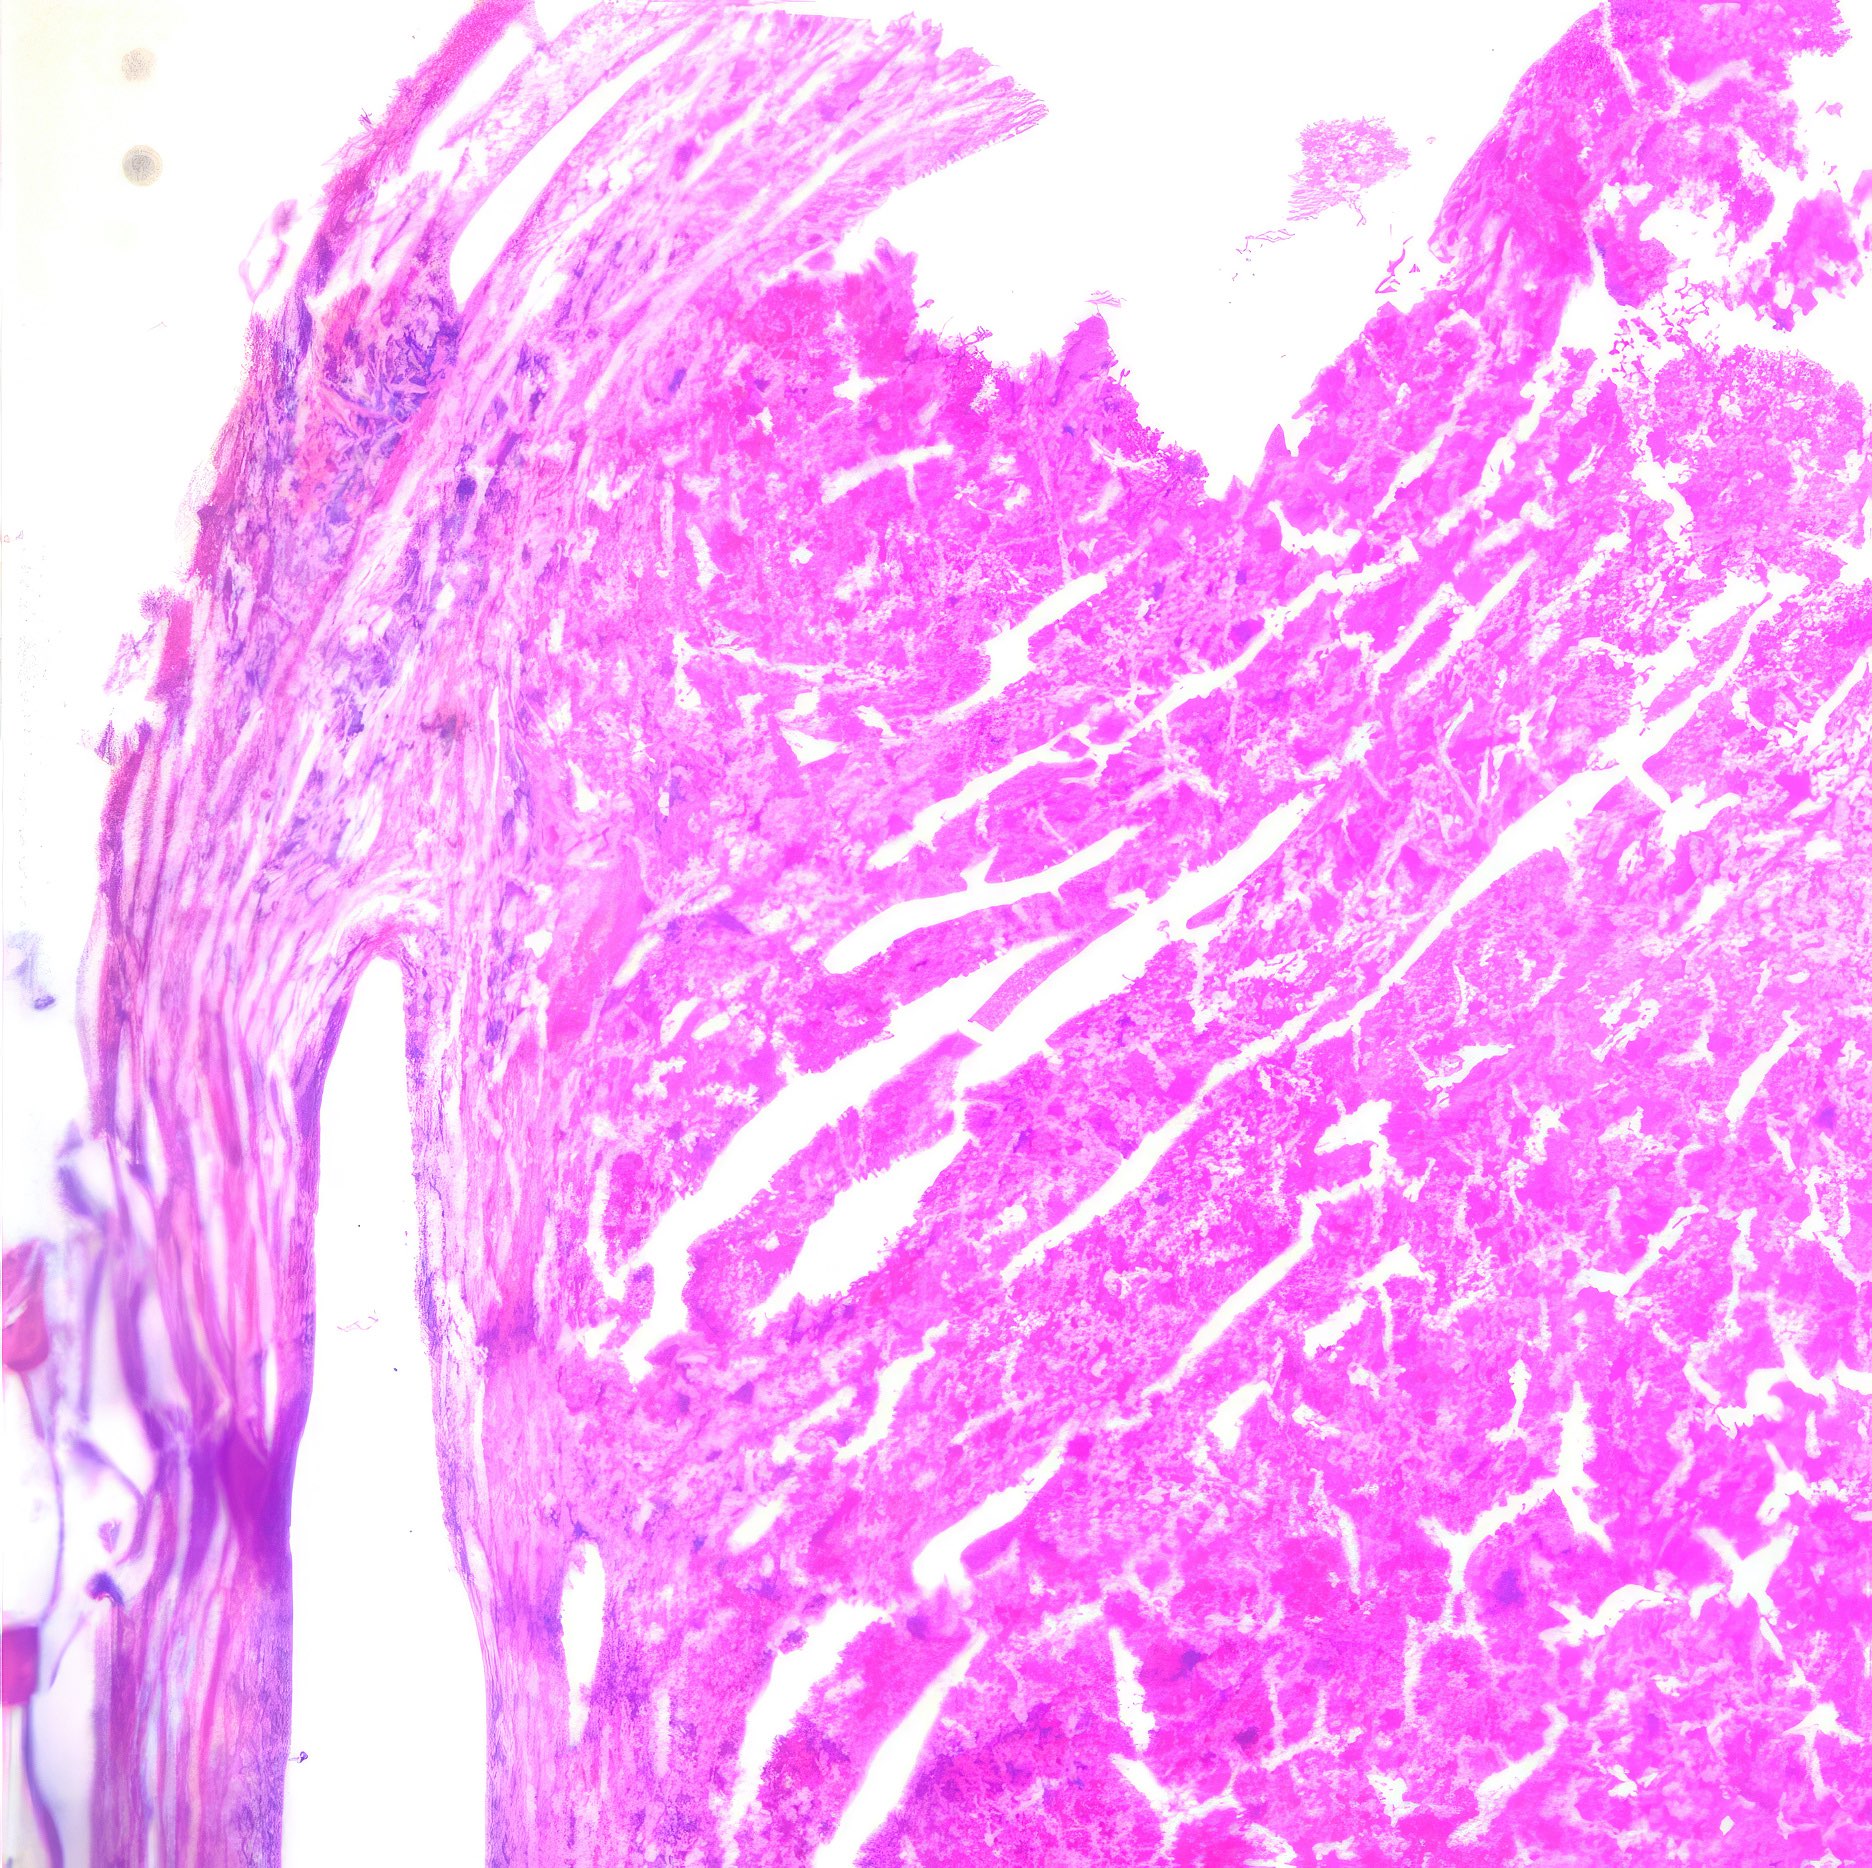

Histologie

Die histologischen Bilder (Abb. 1 und 2) bestätigen die zytologische Diagnose. Weite Teile des Gewebes sind durchsetzt von Tumorzellen, die nur angedeutet Verbände bilden und deutlich polymorphe Kerne aufweisen.

Abbildung 1 und 2: Histologische Bilder desselben Falles, HE-Färbung, Abb.1: Obj. 10x, Abb. 2: Obj. 20x